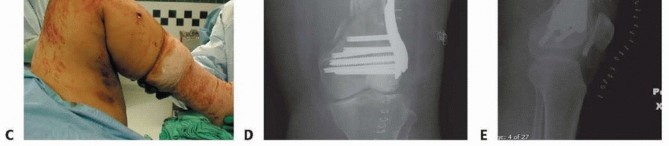

### TECH FIG 9 • A. Patient with significant metaphyseal bone loss from an open injury shown on CT scan. - B. The postfixation radiograph shows the void. C. Placement of OsteoSet beads impregnated with vancomycin (off-label use) to fill the void and provide osteoconductive material for healing. Multiple locking screws are used in the epiphysis because of the short length of these distal fragments. The largest screws available for the epiphysis should be used. ### Bone Grafting The metaphyseal comminution may require bone grafting or the use of bone substitutes in cases of open fractures with bone loss. The exact type and need vary and should be based on the surgeon's experience ( TECH FIG 9). In closed fractures, avoiding stripping of the medial soft tissues often allows for healing without bone grafting. 486 In open fractures with significant bone loss, we have had good success with the use of bone substitutes such as calcium sulfate (+/- antibiotics mixed in; off-label use), avoiding the need for later grafting (see FIG 11A-H). Hemostasis is achieved throughout the procedure or after the tourniquet is released. A tourniquet can be used to help minimize bleeding and improve visualization, especially for articular reconstruction. Often, a sterile tourniquet is used because of the temporary bridging external fixator that is in place. After adequate irrigation (before bone graft or substitute placement if used), a drain is placed in the knee joint and brought out laterally.

---

### TECH FIG 10 • A. Closure of the arthrotomy. B,C. Full flexion and extension of the knee after definitive fixation and closure. As seen in final AP (D) and lateral (E) radiographs, the metaphyseal comminution is bridged and left undisturbed. - Standard Wound Closure Closure of the arthrotomy is performed with figure-8 0 Vicryl sutures. This is reinforced by a running 2-0 FiberWire (Arthrex, Inc., Naples, FL) or Ethibond suture ( TECH FIG 10A). The subcutaneous tissue is closed with 2-0 Vicryl. The skin is closed with staples, as are the percutaneous stab incisions. The knee is flexed and extended fully to ensure restoration of motion as well as to break any adhesions in the quadriceps that may have formed while the temporary bridging external fixator had been in place ( TECH FIG 10B,C). The final radiographs are taken in the operating room ( TECH FIG 10D,E). 1. ## Open Reduction and Internal Fixation of the Distal Femur with Locking Plates (Type A or Nondisplaced Type C1 or C2) This technique can be used regardless of the locking plate system used. Each system's technique guide should be reviewed before use as each system has its own idiosyncrasies. Variations in plate application as well as reduction tools and techniques are unique to each system. See comments earlier regarding temporary use of an external fixator or distractor. ### Limited Lateral Approach A lateral incision measuring about 5 to 6 cm is made starting at the level of the joint and extending proximally in line with the shaft. The distal extent is curved slightly toward the tibial tubercle, as in the lateral approach ( TECH FIG 11A,B). The iliotibial band is incised in line with the skin incision ( TECH FIG 11C). The dissection is carried down to the lateral femoral condyle. The lateral aspect is exposed enough for plate placement ( TECH FIG 11D). A Cobb elevator is used to create a plane submuscularly up the lateral shaft of the femur for placement of the plate.